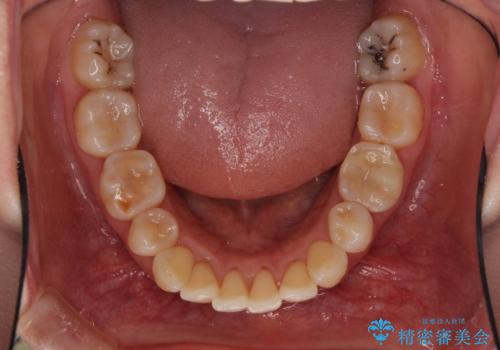

- 上の前歯の出っ歯を治したいとのことで来院された患者様です。

後戻りによる再矯正というもともあり、インビザラインを希望されていました。

上顎の歯は後方移動とIPR(歯と歯の間を削る)によって口元が引っ込むように、下顎は歯列全体の拡大とIPRによって上顎とバランスよく咬み合うように設計し、インビザラインにより治療を行うこととしました。

治療を開始して暫くして、勤務先から2年以上帰国することができず、それまでの移動がほとんど後戻りしてしまい、帰国後に再度後戻りをリカバリーするための治療を行うこととなりました。

5年以上の治療期間がかかりましたが、気になっている部分を改善することができました。